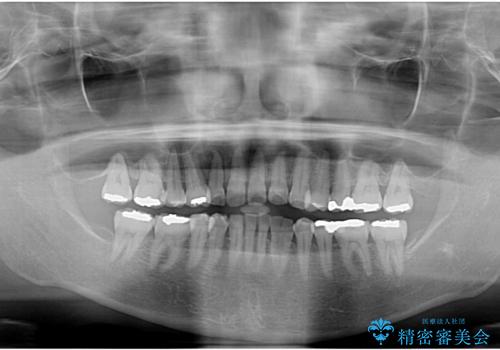

- 長年前歯の歯並びで悩んでいるとのことで来院された患者様です。

機能的なことを考えると八重歯となっている犬歯は抜歯せず、歯列を改善することが望ましいとされますが、数十年もの間犬歯がない咬み合わせで問題なく過ごしてきたため、八重歯を抜歯することで、手っ取り早く歯列を改善することとしました。

また、当初は予定しておりませんでしたが、歯列が整ったことで前歯の歯の色や形が気になり、矯正治療後にオールセラミッククラウンにて補綴治療することとしました。